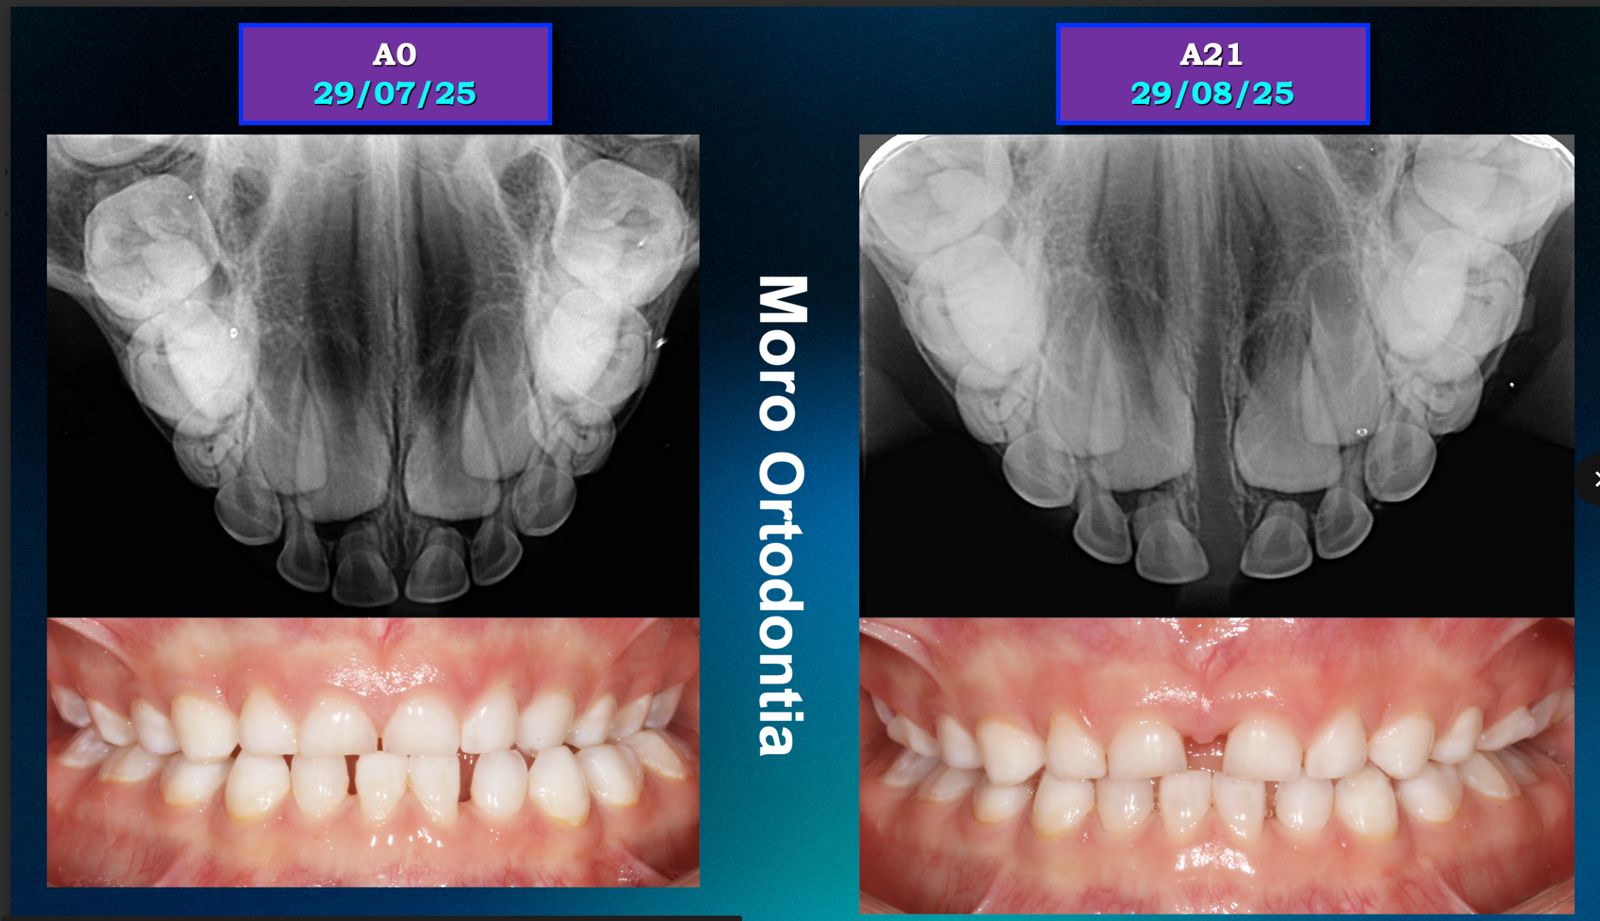

O Invisalign First é o sistema de alinhadores transparentes desenvolvido especialmente para crianças em fase de crescimento. Ele corrige problemas de mordida e alinhamento de forma confortável, removível e praticamente invisível, tornando o tratamento muito mais fácil para os pequenos e para os pais.

Sim. Os alinhadores do Invisalign First são capazes de realizar movimentos de expansão, criando espaço para os dentes permanentes nascerem de forma adequada, quando indicado pelo ortodontista.